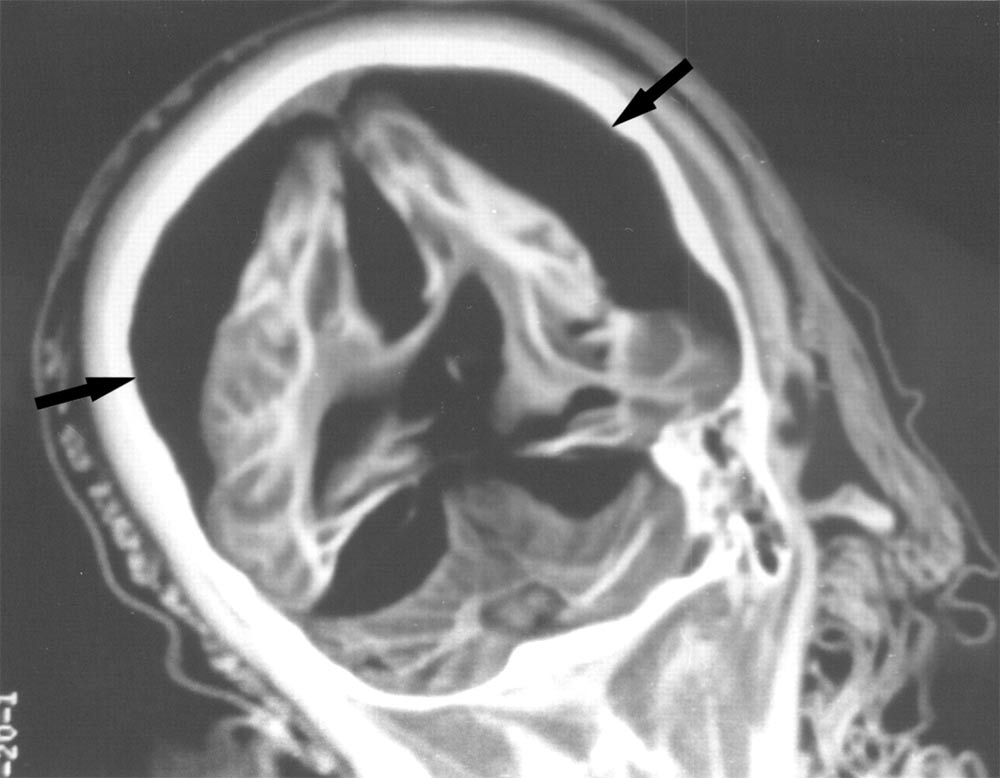

Eye Orbits

Shown here, the CT scan of the brain of the 6-year-old female mummy who was likely struck by lightning. The scan, released in December 2003, shows her orbits with presence of eyes, optic nerves (arrows), and orbital muscles.